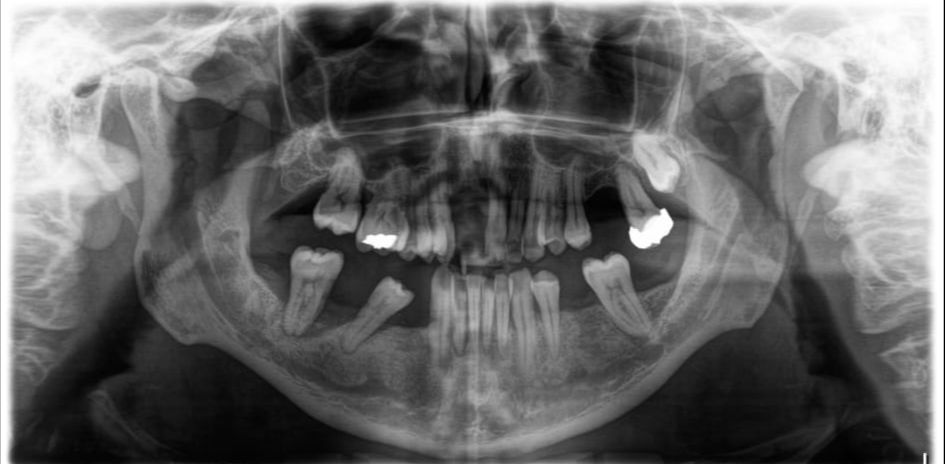

Zahnklinik TĂŒrkei: 8 Implantate setzen mit All-on-4

I. Befund des gesamten Gebisses / Behandlungsplan

Oberkiefer

11 BM f x BM 21

12 SKM f x SKM 22

13 BM f x BM 23

14 BM x x BM 24

15 SKM x x SKM 25

16 BM x f BM 26

17 x x 27

18 f f 28

Unterkiefer

48 f f 38

47 x x 37

46 BM f f BM 36

45 SKM x f SKM 35

44 BM )( x BM 34

43 BM x x BM 33

42 SKM x x SKM 32

41 BM x x BM 31